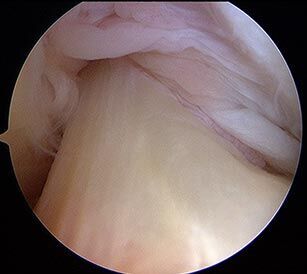

Gesundes-Kreuzband

Zunächst erfolgt eine Arthroskopie (minimalinvasive Gelenkspiegelung) des betroffenen Knies bei der die Verletzung des Kreuzbandes genau untersucht und auch dokumentiert (Foto, Video) wird. Gleichzeitig werden auch weitere Verletzungen, z.B. Meniskus- oder Knorpelschäden behandelt.